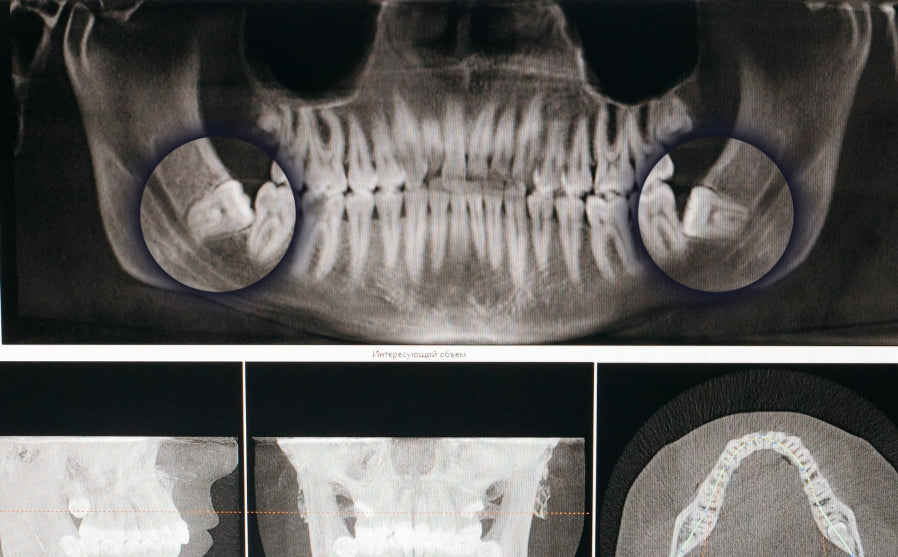

2. Eingeklemmte Weisheitszähne

Weisheitszähne, die im Kiefer stecken bleiben, nennt man impaktierte Zähne. Sie können entweder teilweise durchbrechen oder vollständig unter dem Zahnfleisch und Knochen verborgen bleiben.

- Teilweise impaktierte Zähne: Hier ragt ein Teil des Zahns aus dem Zahnfleisch, während der Rest im Kiefer eingeschlossen ist. Das klingt harmlos, birgt jedoch einige Risiken. Die Stelle, an der Zahn und Zahnfleisch aufeinandertreffen, ist schwer zu reinigen. Bakterien und Speisereste können sich ansammeln, was zu schmerzhaften Entzündungen und Infektionen führt.

- Vollständig impaktierte Zähne: Diese bleiben komplett im Kiefer verborgen. Hier können sich auch Zysten bilden, was jedoch äußerst selten ist.

Wenn du unter unerklärlichen Symptomen leidest wie Knieschmerzen, neurologischen Störungen, Gelenksproblemen, chronischer Müdigkeit usw., wo trotz intensiver Untersuchungen keine eindeutige Ursache gefunden werden kann, könnten NICOs/FDOKs eine Möglichkeit sein, die in Betracht gezogen werden sollte. Eine Diagnose kann durch eine 3D-DVT-Aufnahme (Digitale Volumentomografie) gestellt werden, die den Kieferknochen detailliert darstellt und entzündliche Veränderungen sichtbar macht. Diese können dann durch eine gezielte Reinigung des betroffenen Kieferabschnitts behandelt werden.